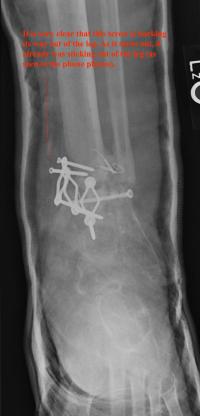

Post-infection X-Rays of the damaged right & left legs / ankles

After the last surgery Liam developed Staphylococcal (staph) infection as well as Osteomyelitis on the bone. Liam went to the ER of

Tempe St. Luke with a temperature of over 104 degrees and severe pain of the left leg. Liam was released from the ER with a diagnosis of

Gastroenteritis and instructions to follow up with a visit to Dr. Armendariz. Four days later and with a continued very high temp, Liam was

seen by Dr. Armendariz. Dr. Armendariz immediately performed 3 surgeries to clean out the infected areas of both the left and right leg and

to place wound vacs on the damaged areas of the legs.

An interesting point to note, as it applies to the second and third x-rays (from the left), is the placement of the last screw at the bottom

of the right legs fibula plate. Notice how Dr. Keller completely missed the plate. Not only is the screw useless, but it has started protruding

in such a way as to cause severe pain and require padding to keep from bursting through the skin. A later surgery is planed for the screws

removal.